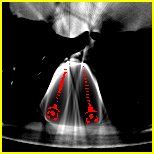

SE-Net. To restore a clean sinogram from , conventional methods remove the second term in (4) through inpainting. Following this concept, DuDoNet takes linearly interpolated sinogram and binarized metal trace as inputs for sinogram domain enhancement, where (, ). Here, we observe that the second term in (4) is actually a function of . Therefore, we propose to directly utilize the knowledge of metal mask projection . As shown in Fig.1, our SE-Net uses a pyramid U-Net architecture [7], which takes both and as inputs. To retain the projection information, goes through average pooling layers and then fuse with multi-scale feature maps. As metals only affect part of the sinogram data of the corresponding projection pathway, SE-Net learns to correct sinogram data within the metal trace and outputs the enhanced sinogram . Sinogram enhanced image is reconstructed by the differentiable RIL first introduced in [8], that is, .

Sinogram data is inherently periodic along the projection direction, while DuDoNet uses zero padding for convolutions in SE-Net which ignores the periodic information. Here, to offer more useful information for convolution, we propose a new padding strategy for sinogram data using periodic padding along the direction of projection angles and zero padding along the direction of detectors, as shown in Fig. 6.